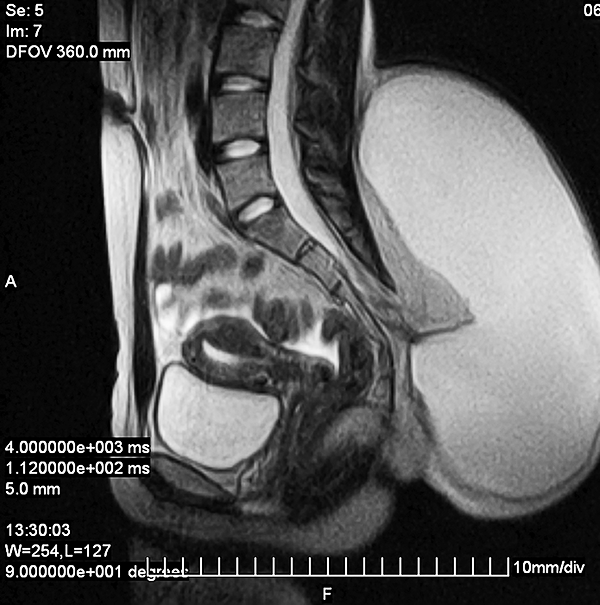

Presentamos un segundo paciente, perteneciente al grupo 2, de una paciente adulta joven, de 19 años, con antecedentes de una pequeña tumoración lumbar de aproximadamente 1.5 cm de diámetro que refiere tener desde el nacimiento (patología congénita). Refiere tener un crecimiento paulatino de dicha lesión hasta alcanzar un diámetro aproximado de 12 cm a los 18 años. Durante el siguiente año, la paciente consulta por presentar dicha tumoración de aproximadamente 25 cm de diámetro, la cual había aumentado de tamaño en asociación a un proceso infeccioso local secundario a un traumatismo leve en esa región (figs. 2 y 3). Se confirma el diagnóstico de un lipomeningocele y se le solicitan los estudios pertinentes. Se decide la intervención quirúrgica de la lesión, reparando el defecto mediante la exéresis de la pared del meningocele, con formación de un nuevo fondo de saco dural (figs. 4 y 5). La paciente evoluciona favorablemente, sin presentar síntomas de médula anclada al momento.

Figura 2: Lipomeningocele lumbar congénito.

Figura 3: Corte sagital de secuencia T2 del lipomeningocele: imagen prequirúrgica.

Figura 4: Imagen post-operatoria luego de la reparación del defecto espinal congénito.

Figura 5: Corte sagital de RM secuencia T2 del lipomeningocele: imagen postquirúrgica.